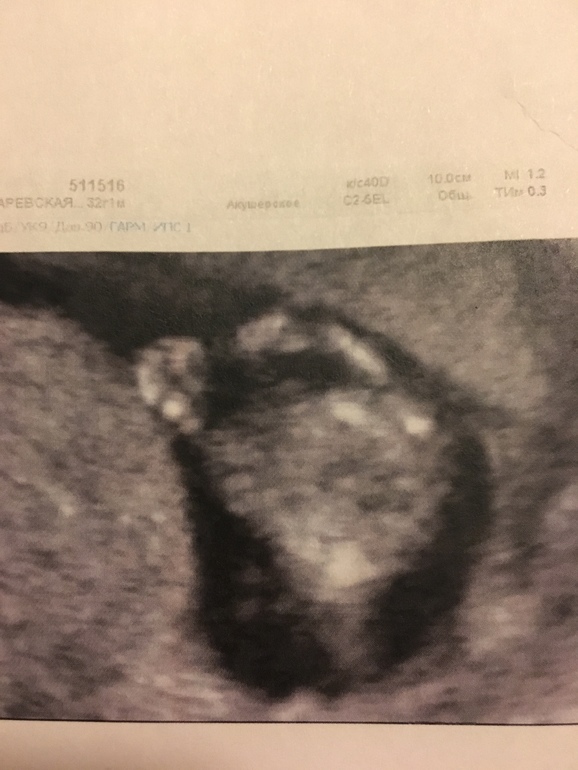

Вот тут косточку видно:

А тут просто ручкой машет: